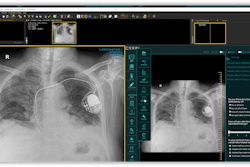

In their study, the researchers wanted to assess the performance of ChestEye Quality (Oxipit) in providing quality assurance for chest x-ray interpretations. They applied the software to a retrospective sample of 3,892 chest radiographs gathered from a single institution over a six-month period.

The software first uses a deep-learning algorithm to analyze chest x-rays for findings. Next, a natural language processing algorithm then evaluates the associated radiology report to see if any clinically significant findings were missed. In cases flagged by the software, a radiologist reviews the exam to confirm if there's a mismatch and then determines if any mismatches were clinically significant.